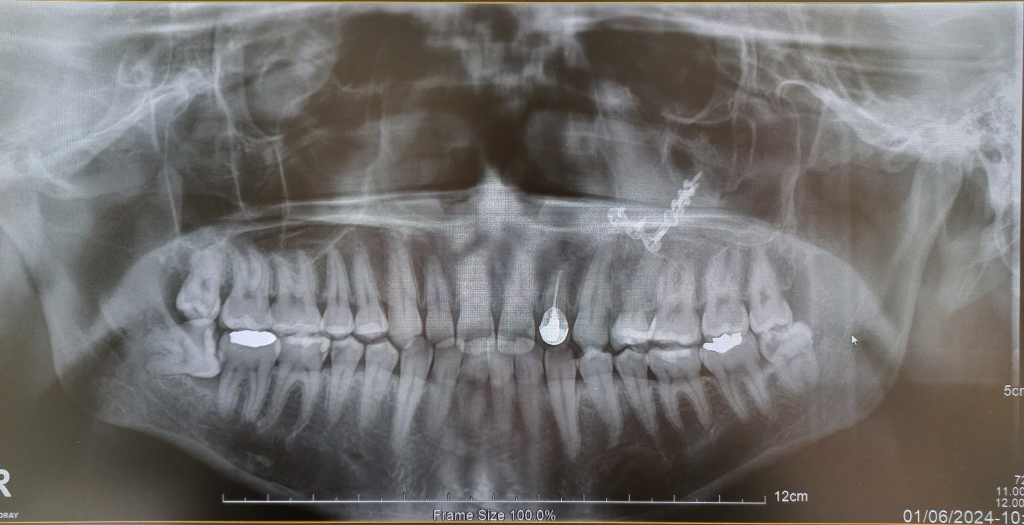

A치과에서는 사이충치 1곳 치료필요하고 사랑니 우측 하단 사랑니 1개 빼야한다고 했고 B치과 가봤더니 충치 8~9개 치료해야하고 사랑니도 4개 다 뽑아야한다고 하네요

과잉진료로 봐도 되는 정도인가요? 아니면 의사분들마다 의견차이가 이렇게 심할 수도 있는건가요?

사랑니는 치과의사마다 다를 수 있고 충치 갯수는 한곳으로 보이진 않고 다수가 보이고 있습니다.

우측 하단 사랑니는 무조건 뽑아야되는 사랑니인거 같고 나머지 사랑니도 관리가 안될꺼 같으니 뽑으라고 말한거 같습니다. 그리고 엑스레이상으로 인접면 충치가 다수보이긴 합니다.

2. 충치에 대해서 보려면 파노라마 사진(큰 사진)보다는 작은 치근단 사진을 보는 것이 좋습니다.

3. 사랑니의 경우 파노라마 사진 상에서는 아래 2개는 일단 뽑는 것이 좋을 것 같습니다. 특히 아래 우측 사랑니는 옆 어금니에도 영향을 주고 있기 때문에 너무 늦지 않게 뽑는 것이 좋을 것 같습니다.